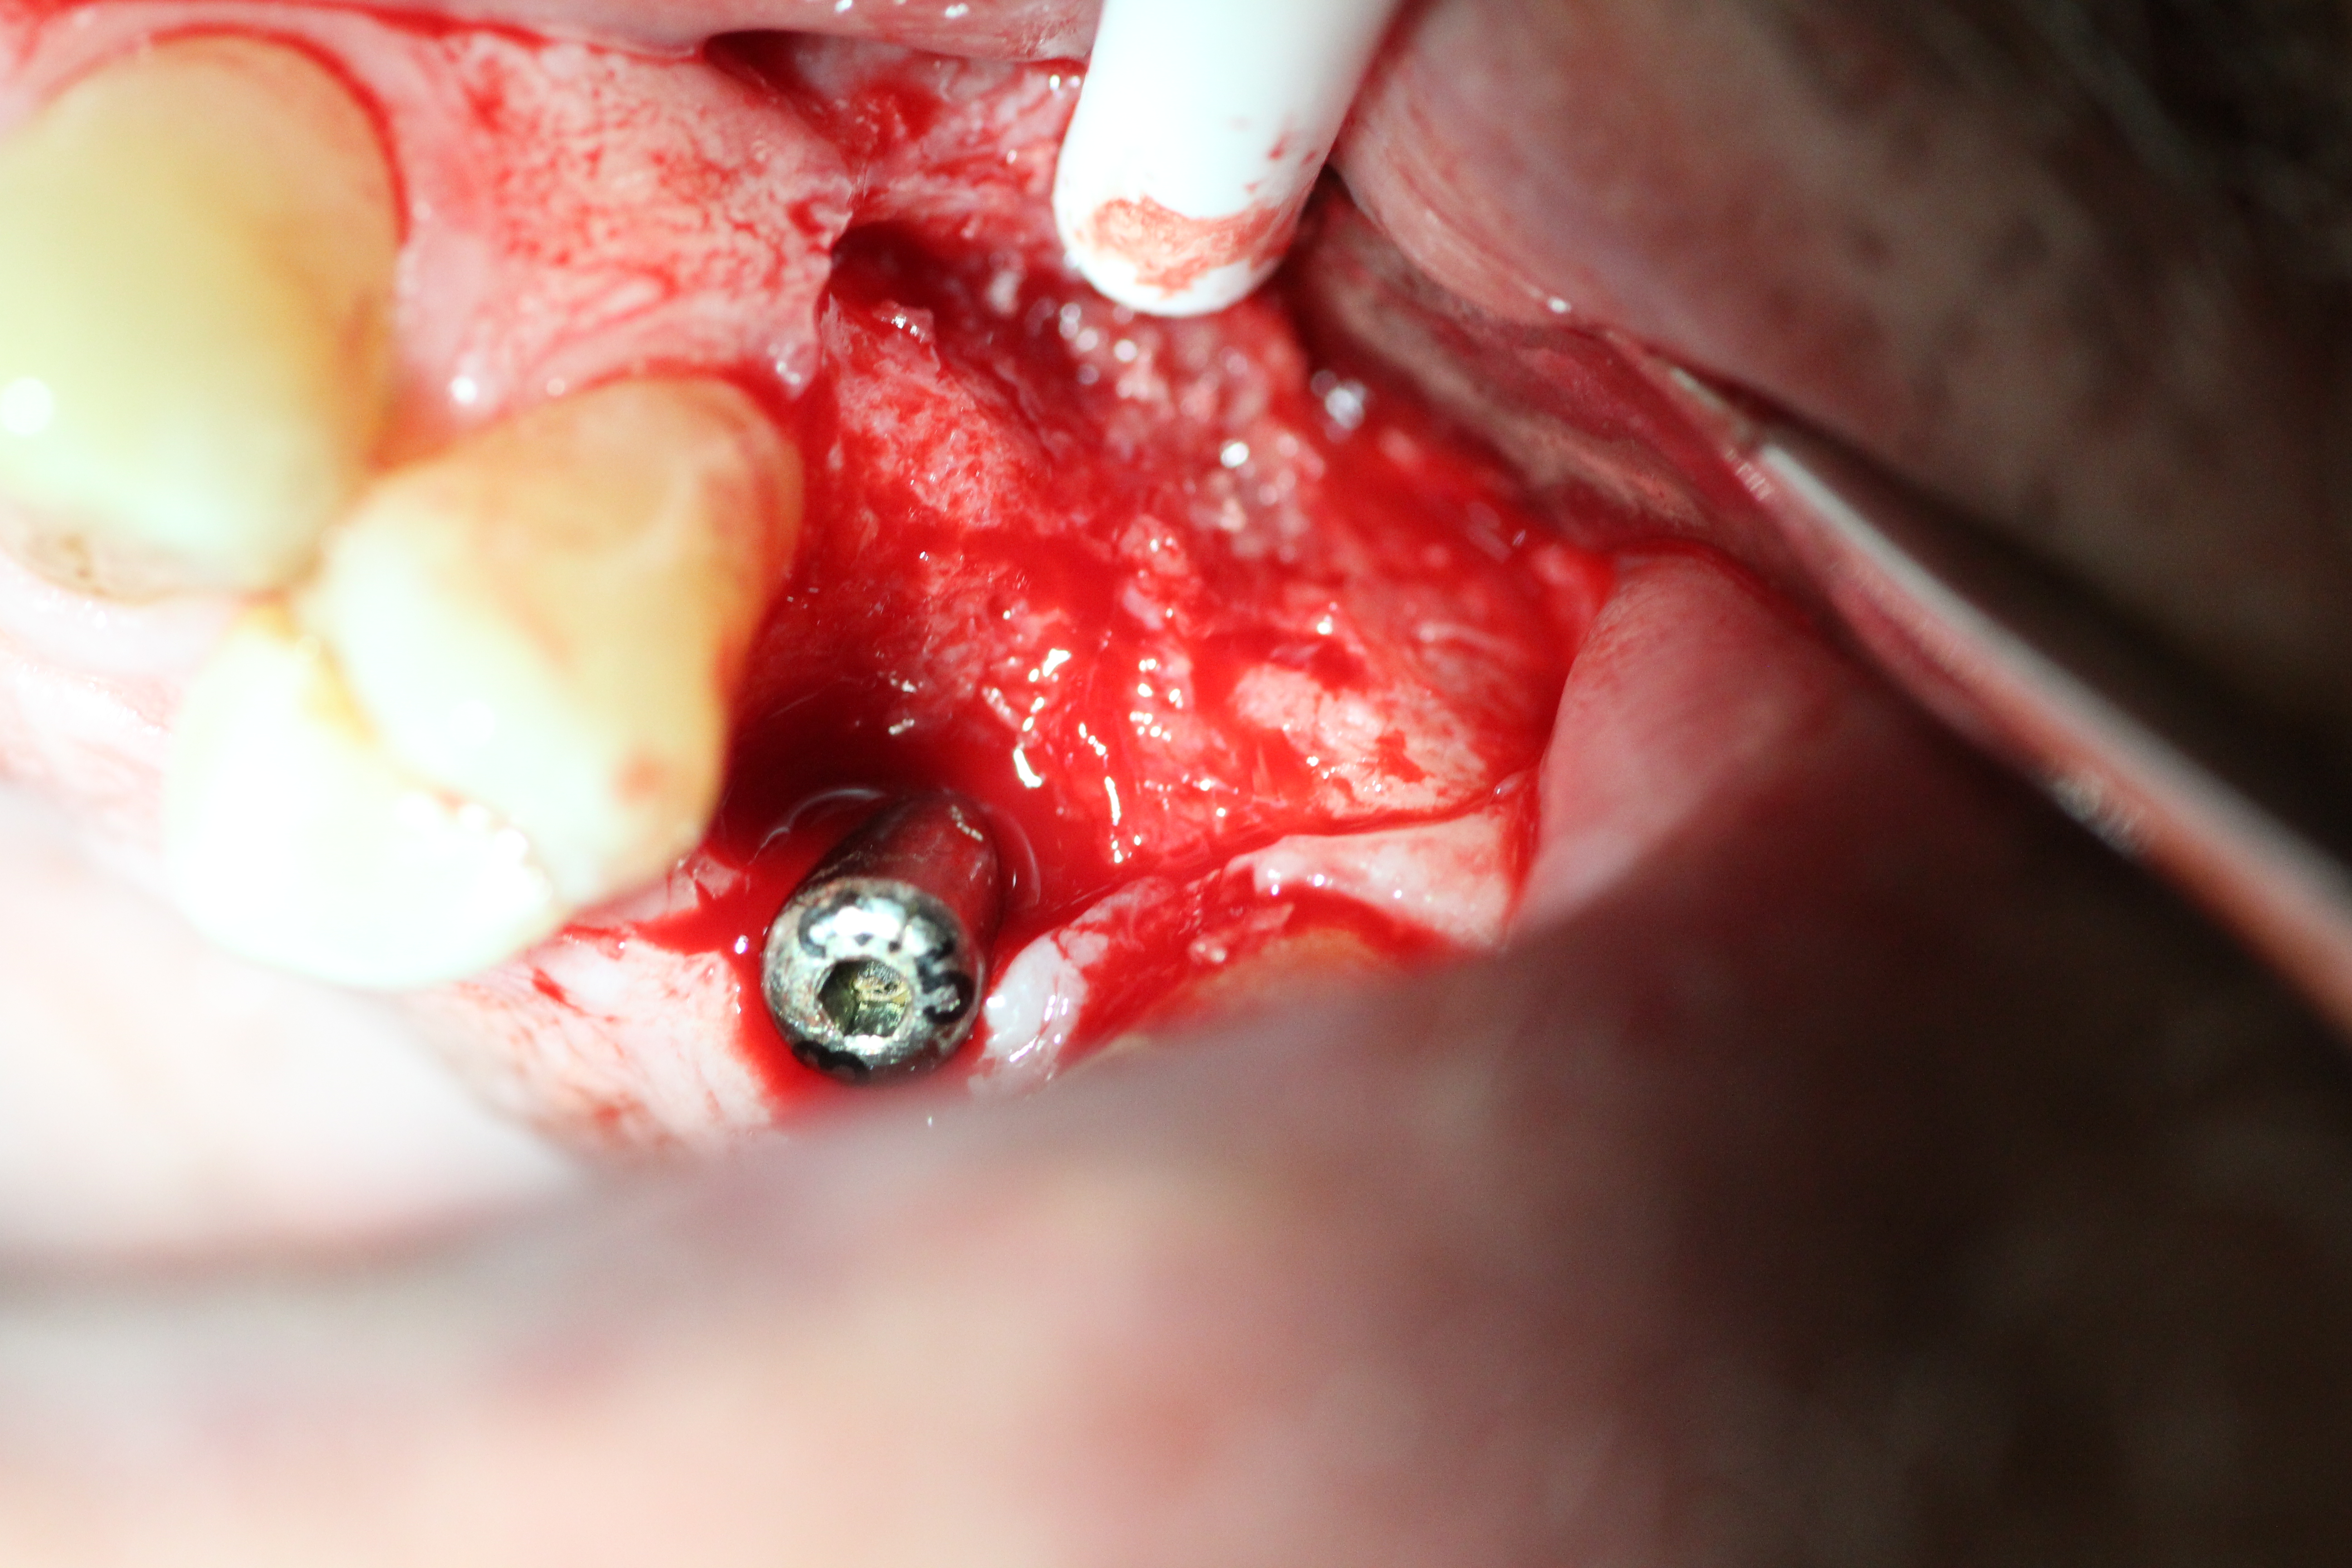

Case #2

Extraction and immediate implant placement with guided bone regeneration.

- Implant is in place.

- Bony defect measuring 3mm x 10 mm.